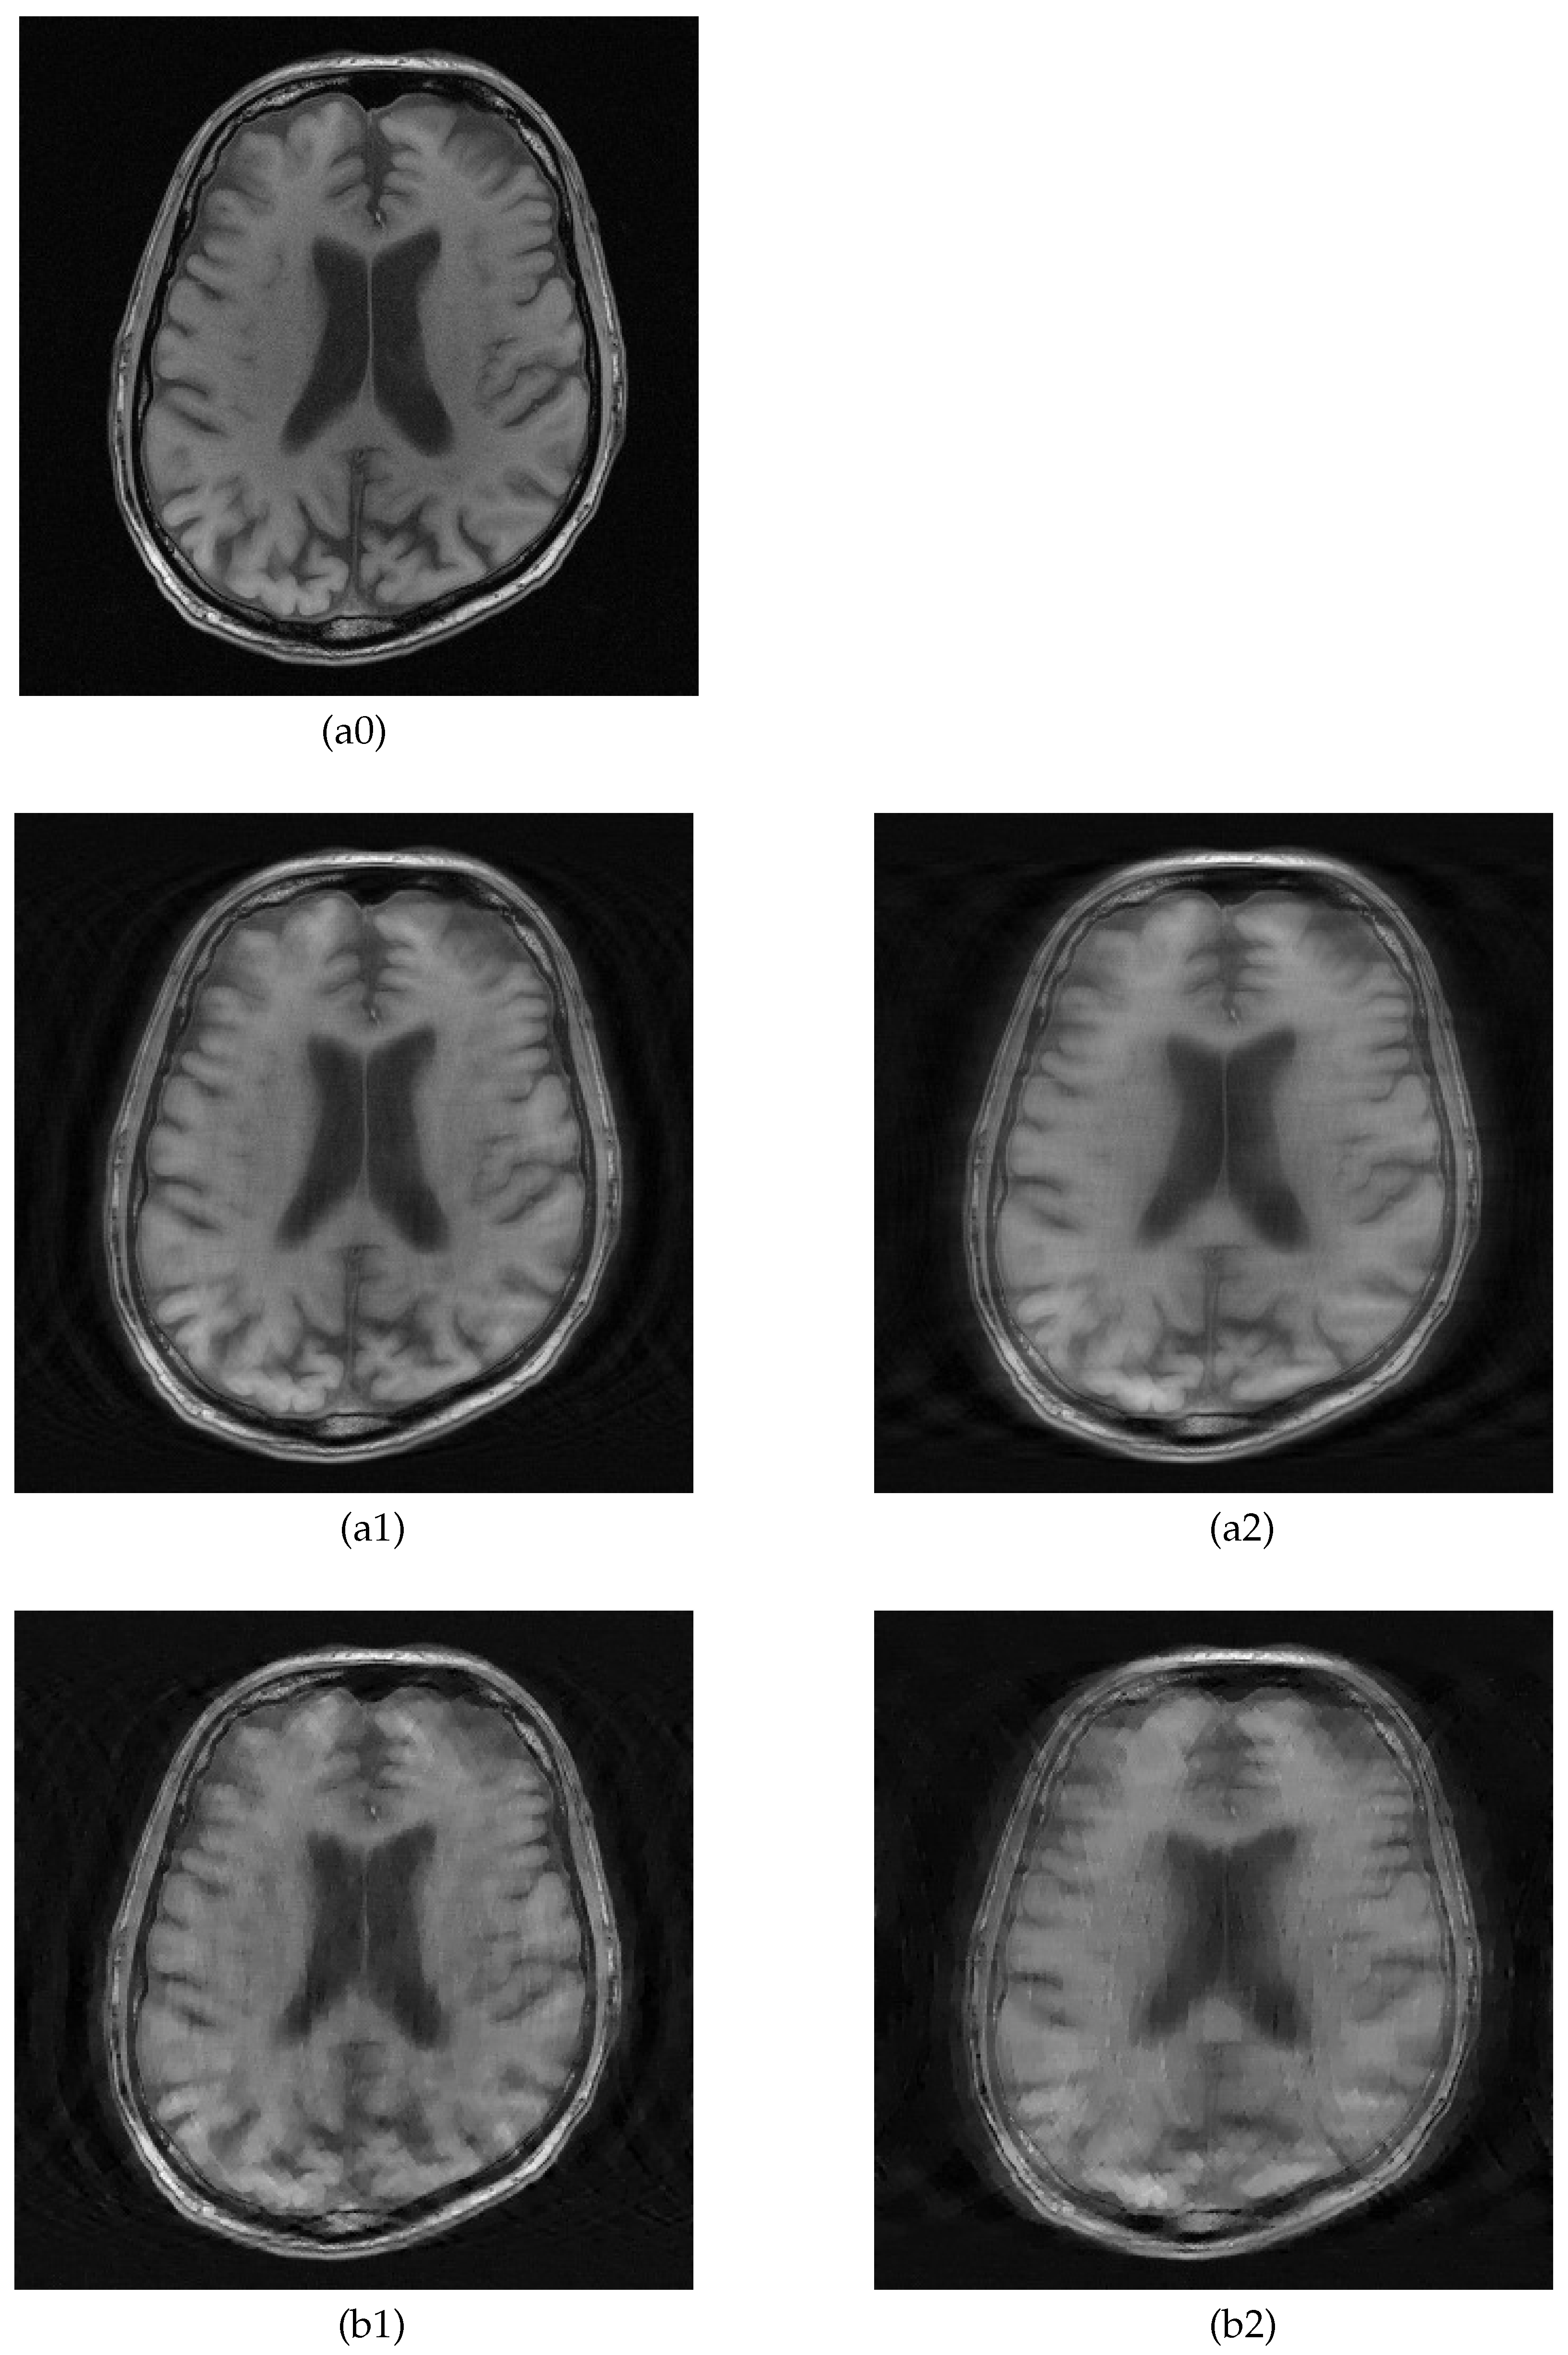

5.2. MRI Image Recovery

| Brain A | 27.7 | 24.1 | 0.642 | 0.524 | 26.7 | 22.3 | 0.637 | 0.493 |

| Brain B | 27.7 | 24.6 | 0.668 | 0.494 | 26.8 | 22.7 | 0.644 | 0.474 |